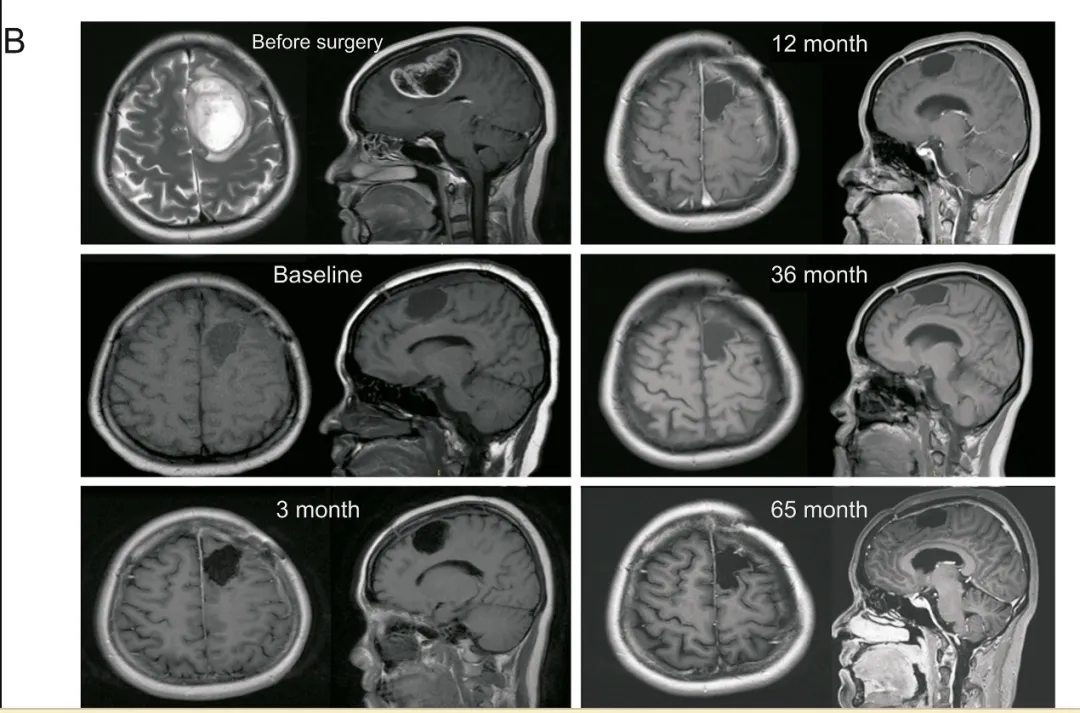

《药物分析杂志》报道了我国一例37岁胶质母细胞瘤患者的抗癌奇迹——其接受DC疫苗治疗后,实现超5年长期生存。该患者于2017年因找词困难、言语不流利就诊,最终确诊为多形性胶质母细胞瘤(WHOⅣ级),MRI显示左额叶存在3.8cm×5.8cm×3.6cm的增强性病灶。后续患者先接受手术切除、标准放化疗及辅助化疗;在放化疗前,还通过白细胞分离术收集外周血单核细胞(PBMC),用于制备自体DC疫苗。待同步放化疗完成1周后,患者开始DC疫苗回输治疗,所用疫苗装载了mRNA-新抗原、mRNA-TAA、次氯酸(HOCl)氧化肿瘤裂解物等多种形式的肿瘤抗原,以提升治疗效果,患者共完成42次DC疫苗回输。

结果显示:术后即刻卡氏功能状态评分(KPS)为70分,且言语、找词困难症状逐渐缓解;截至2022年11月,复查MRI未发现复发迹象。至此,该患者的无进展生存期(PFS)长达69个月(超5年),达到“临床治愈”状态。

▲图源“ScienceDirect”,版权归原作者所有,如无意中侵犯了知识产权,请联系我们删除

综上,这位患者经同步放化疗联合DC疫苗治疗后,实现69个月无进展生存的案例,为胶质母细胞瘤患者及DC疫苗研发团队注入了强心针。这提示联合DC细胞免疫治疗对GBM患者的长期管理安全可行,即便面对凶险的胶质母细胞瘤,只要不放弃希望,就有战胜疾病的可能。